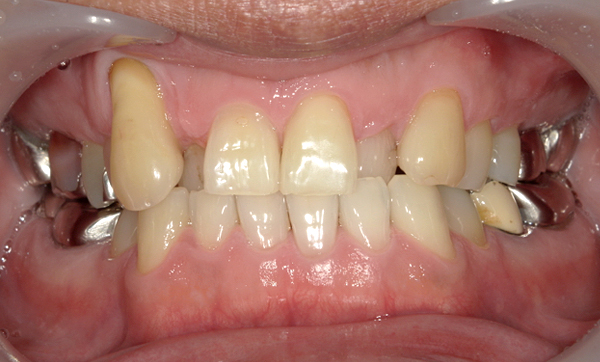

抜歯を伴った部分矯正の症例

当院は基本的には抜歯せずに、ディスキング(歯の横の面をエナメル質の範囲内で多少削る)にて歯列矯正しています。

ただし、部分矯正でも必要であれば抜歯を行なって治療を行うこともございます。

また、歯を並べるスペースが元々確保できる場合は、抜歯もディスキングも行わずに治療します。

| Before | After |

|---|---|

|

症例詳細:上顎の部分矯正、治療期間:7ヶ月、矯正装置1本:3.5万円+tax、リスク:後戻りの可能性